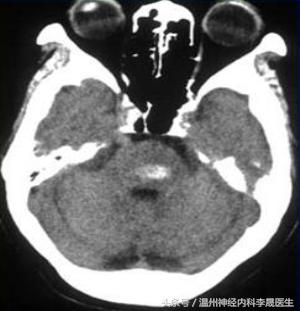

4.小脑出血

小脑齿状核动脉(上动脉)破裂所致,占10%

临床特点: 眩晕呕吐、枕部剧痛、眼震、共济失调、构音障碍,无或轻度意识障碍,无肢体瘫痪。

出血量大,可出现昏迷及脑干受压征象(面瘫,两眼凝视病灶对侧,肢体瘫痪及病理反射);暴发型常突然昏迷,去脑强直、枕骨大孔疝,迅速死亡。

小脑脑叶出血

小脑蚓部出血